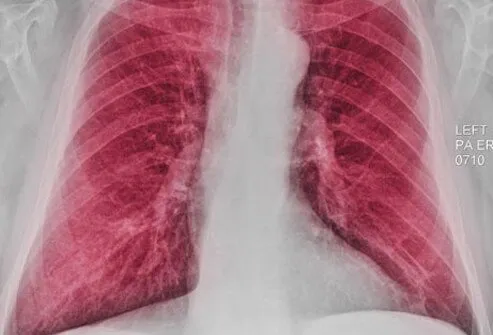

胸部X光

胸部 X 光檢查可能能夠顯示某些COPD患者可能出現的肺部增大(由于過度充氣)。但是,X射線更有用,有助于排除或排除可能導致類似于COPD癥狀的其他問題,例如肺炎。